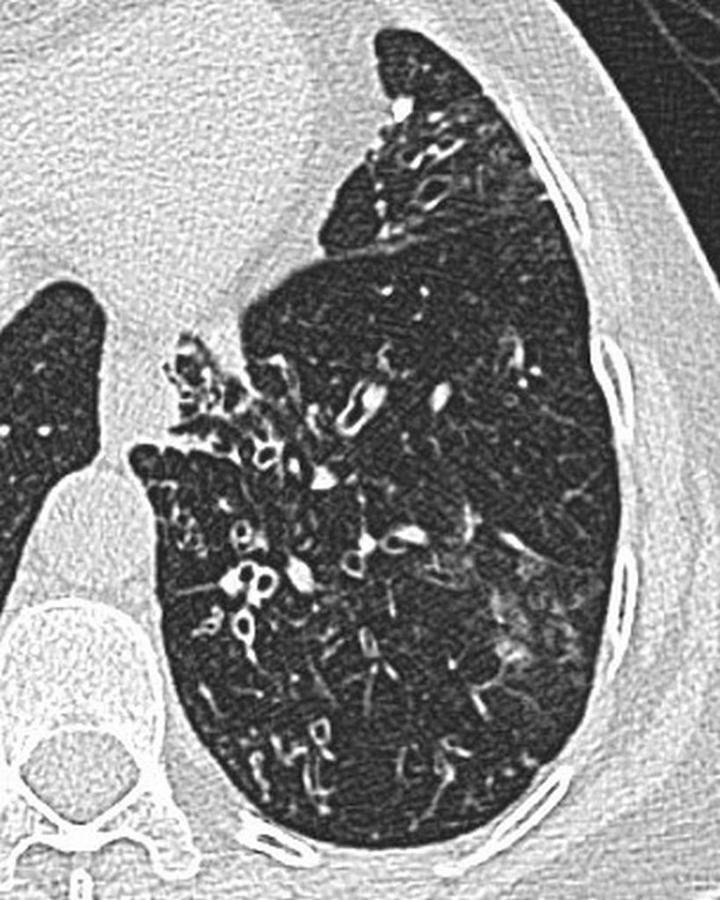

CT

Fleeting alveolar opacities

Centrilobular nodules

High attenuation in impacted mucous

Bronchial wall thickening

Finger in glove

Cylindrical